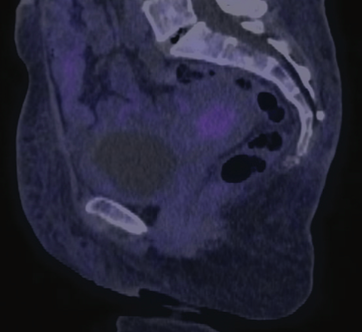

Eight weeks after the end of brachytherapy, a clinical response assessment demonstrated a complete response; however, both the PET-CT and MRI imaging revealed a partial response, as shown in Figures 2 and 3. In addition, the cervical cytology analysis revealed reactive cell changes associated with RT, and a vaginal dome biopsy evidenced extensive necrosis without viable cells in the sample. The patient is currently in a 24-month disease-free period and under surveillance by the medical oncology department.

FIGURE 3. Response Assessment PET-CT Scan. The image reveals the absence of metabolic uptake.